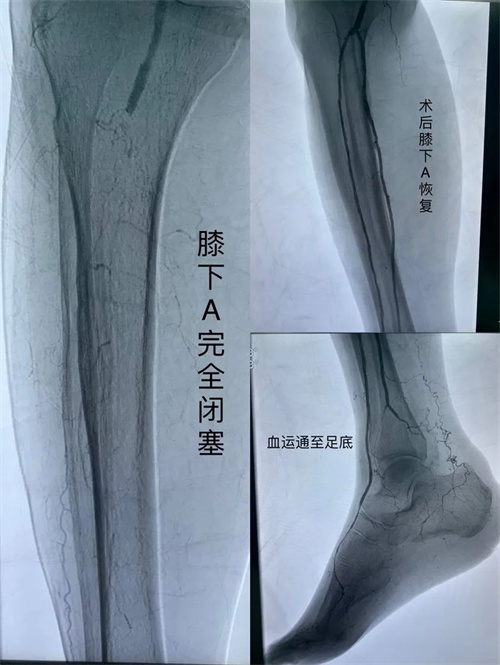

入院后,经过检查发现,孙奶奶股动脉中断闭塞,膝下血管完全闭塞。同时合并伴有慢性心力衰竭、冠状动脉粥样硬化性心脏病、2型糖尿病、高血压3级、肾功能不全、低蛋白血症等。

胡海医生介绍,见到孙奶奶的时候,发现她的情况非常严重:右脚所有脚趾和脚背都已经完全黑掉了,皮肤的破溃创口发红发肿,查体动脉搏动消失,皮肤冰冷,足趾坏疽,孙奶奶也因为剧痛一脸痛苦的表情。 像孙奶奶这种情况,动脉发生狭窄或者闭塞后,导致狭窄或者闭塞动脉远端的血流减少,引起相应肢体供血不足,同时合并多种全身性疾病,若再不治疗,病肢将会持续溃烂、坏死、致残,甚至会有生命危险。必须马上手术,制止疾病的继续发展,改善患肢循环。 考虑到患者年龄大、基础病多、心功能差、血管堵塞严重,手术难度大、风险高,科室团队启动多学科讨论,为患者手术的顺利进行保驾护航。经过全面的术前评估,精细的术前准备,术中采用微创介入技术,先进行球囊扩张,将血管扩开后,再进行支架植入,将闭塞的血管撑开撑大,让下肢血运恢复。 术后孙奶奶恢复情况良好,皮温明显回暖,疼痛情况已基本缓解。 只听过脑梗、心梗 “腿梗”是什么? 人体除了心脑血管容易发生梗塞外,腿也会发生“梗塞”,医学称为下肢动脉硬化闭塞症。简单地说,就是下肢动脉血管硬化,管腔狭窄甚至闭塞,从而出现下肢血液供应不足的一种疾病。 该症发病比较缓慢、隐匿,初起症状较轻时,容易被大家误以为“老寒腿”而忽视。 随着病情发现,患者可出现“间歇性跛行”期,人体活动时,下肢在活动后会出现疲乏无力、痉挛、疼痛等症状,休息1~5分钟后症状缓解或消失,可继续行走。 如果没有积极治疗,就会发展到“静息痛”期。“静息痛”,就是在休息时也会感到下肢尤其是肢端的麻木、疼痛,夜间的疼痛感会加重,令人“坐卧难安”。 如果再进一步发展,就进展到“组织坏死”期。下肢特别是肢端出现经久不愈的缺血性溃疡或坏疽,有时还伴有感染,致残率及病死率高,严重影响人类健康。 要谨记,预防重于治疗。避免长时间站立或坐着不动,同时控制好血压、血糖、血脂,规律运动。 专家推荐 胡海 普外科 血管外科组 副主任医师 江西省研究型医院学会血管医学分会常委 江西省中西医结合学会周围血管疾病专业委员会常委 江西省整合医学学会介入医学分会常委 坐诊时间:周一到周五上午(朝阳院区) 联系电话:13970917464